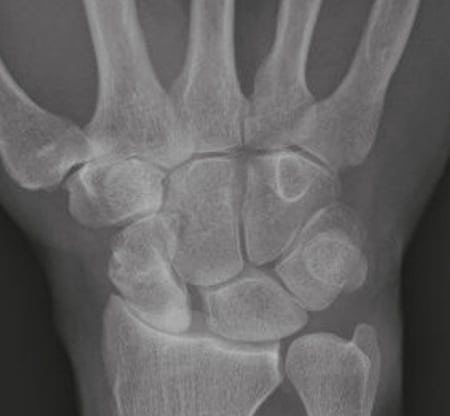

Röntgenbild präoperativ

SNAC-Wrist mit Bewegungs- und Ruheschmerzen.